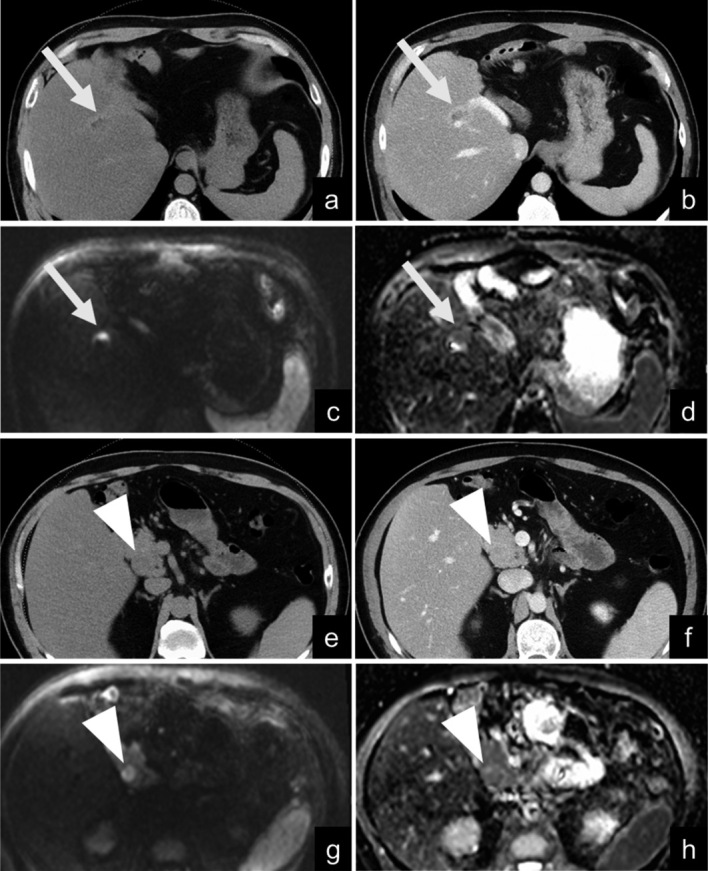

Distinguishing recurrent cholangiocarcinoma lesions from postoperative fibrosis or biliojejunostomy lesions using contrast-enhanced computed tomography (CECT) alone is challenging. This study examined the value of adding diffusion-weighted magnetic resonance imaging (DWI) to CECT for the detection of cholangiocarcinoma recurrence. This single-institution retrospective analysis included 33 patients who underwent cholangiocarcinoma resection between January 2016 and December 2020. Of the patients, 20 were in the recurrence group and 13 were in the non-recurrence group. Two observers independently reviewed the CECT images and subsequently reviewed the combined CECT and DWI images (b-value, 1000 s/mm2), with each image reviewed twice. The diagnostic performance was evaluated using receiver operating characteristic (ROC) curve analysis. Kappa statistics were used to evaluate agreement. The diagnostic performance (area under the ROC curve [AUC]) of both observers improved after the addition of DWI; the AUC improved from 0.614 to 0.918 (P = 0.003) in the first session and from 0.820 to 0.928 (P = 0.20) in the second session for Observer A, whereas it improved from 0.566 to 0.858 (P < 0.001) in the first session and from 0.753 to 0.930 (P = 0.02) in the second session for Observer B. The intraobserver and interobserver agreements improved after the addition of DWI; the kappa value improved from 0.586 to 0.656 for Observer A, from 0.371 to 0.838 for Observer B, from 0.308 to 0.766 in the first session, and from 0.464 to 0.620 in the second session. Adding DWI to CECT improves the detection of cholangiocarcinoma recurrence compared to CECT alone.